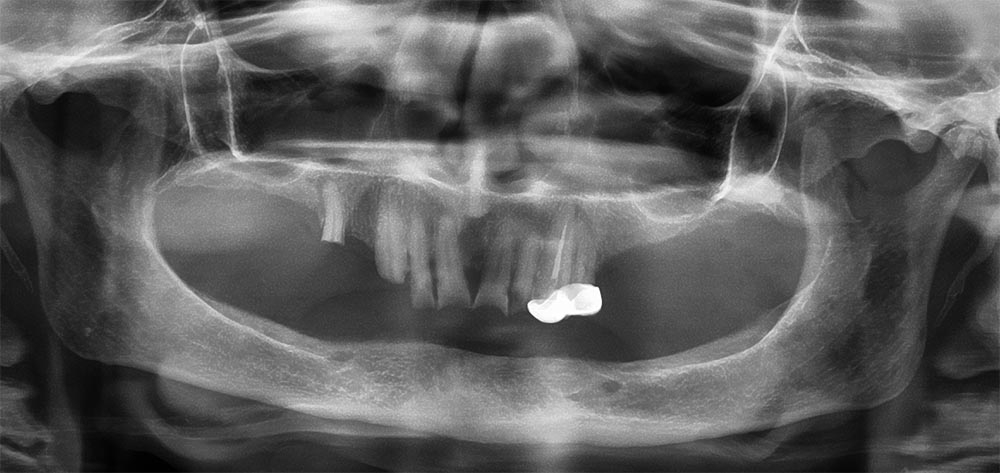

All on 4/ Teeth in a Day

Treatment Photos